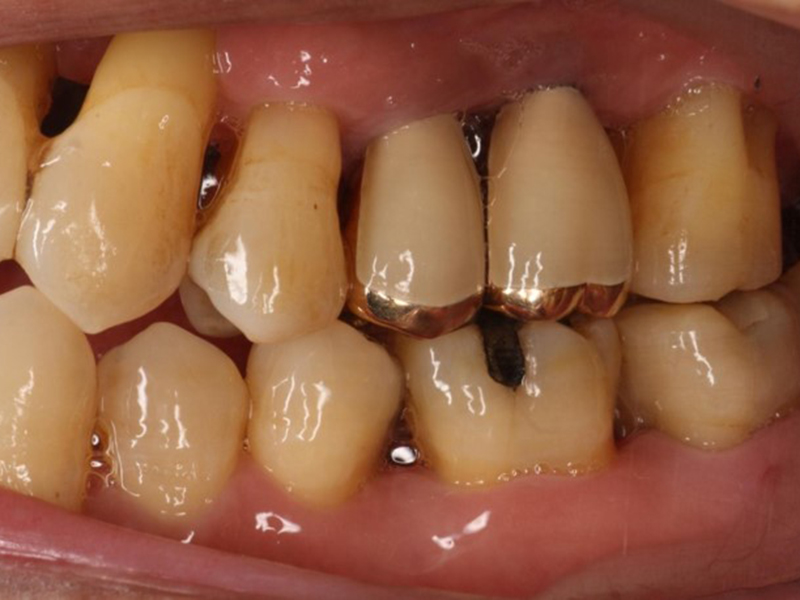

▼ ケース4.Upright症例

初診

治療中